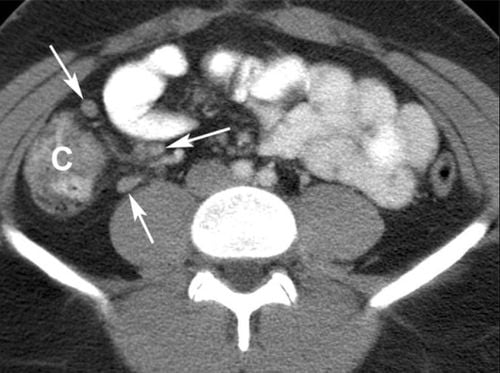

- Siêu âm bụng hoặc chụp CT giúp loại trừ các nguyên nhân khác gây ra triệu chứng.